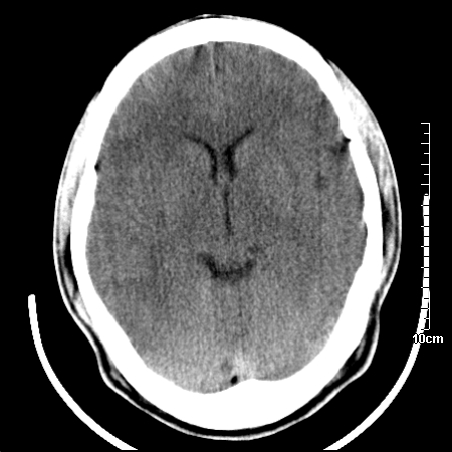

头晕.头痛间断意识恍惚1周 m/21y

4天上述症状加重伴左侧肢体发软,复查ct,

我当时诊断的是1.右侧底节区脑血栓形成

2.考虑少量蛛网膜下腔出血

3.右侧颞叶低密度区考虑脑血管畸形

因病人拒绝进一步检查,反复做工作后,病人做了腰穿,脑脊液化验显示有红细胞,呈现轻度红色

右側额叶、放射冠区灰白质改变,建议ct增强或mri检查

右侧放射冠区混杂密度灶,边缘不清,病人较年轻,结合有发热病史,支持感染性病变,建议密切结合临床可抗感染治疗后复查。